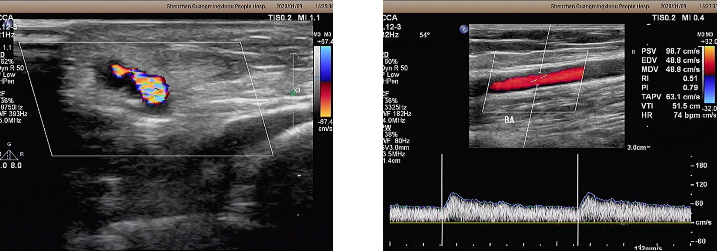

术后超声检查:吻合口上方贵要静脉内径正常,血流通畅。吻合口未见明显狭窄,管腔未见明显血栓。

术后超声检查